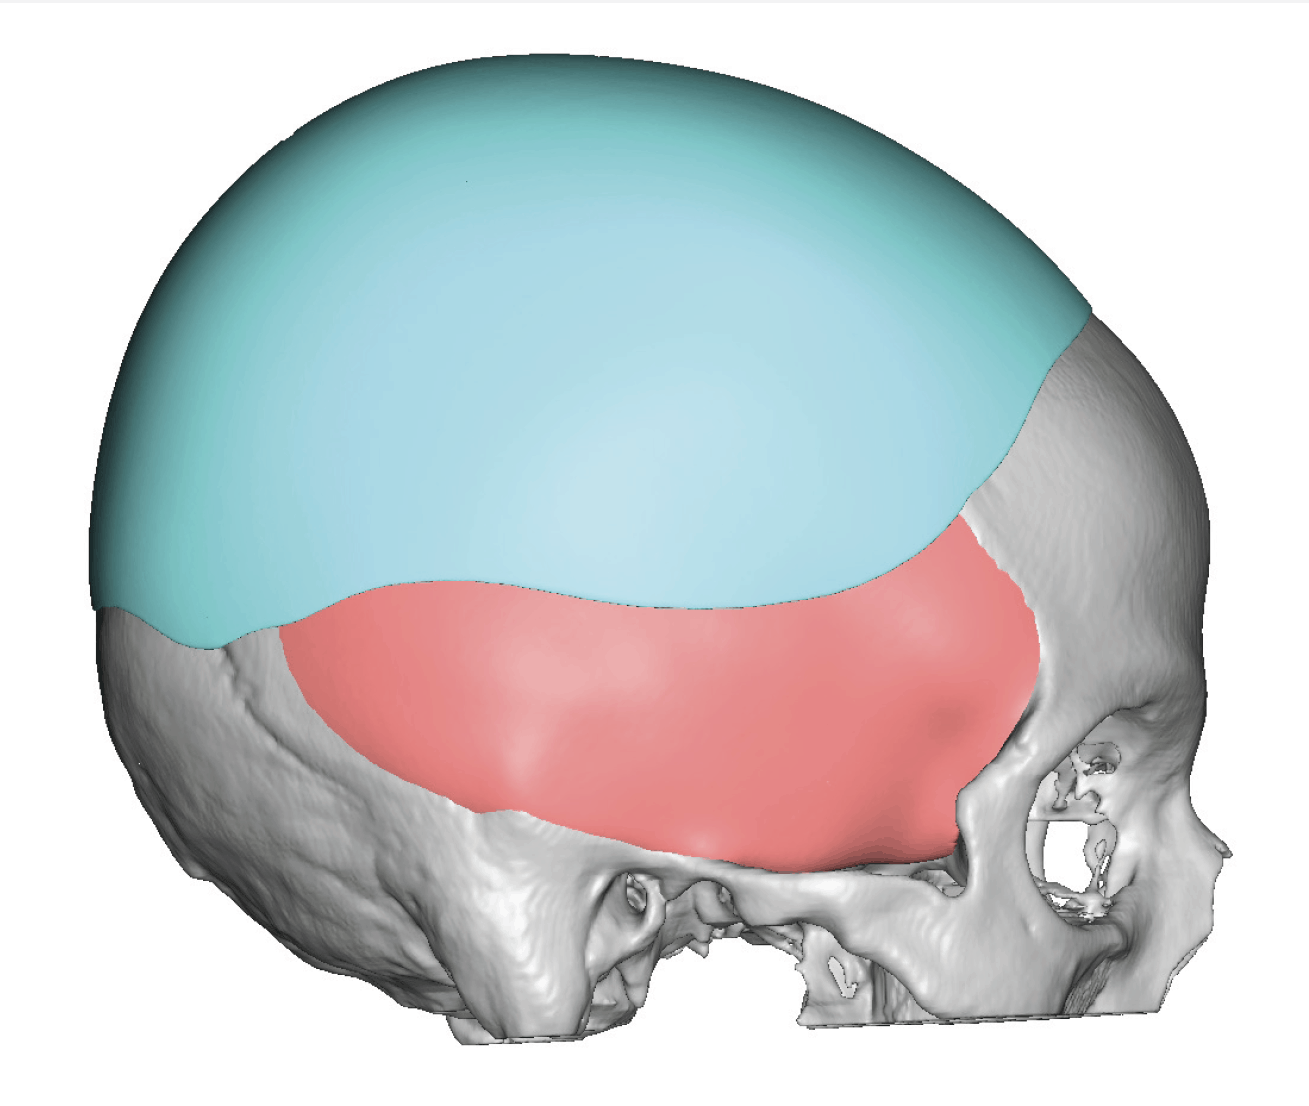

Severe narrowing skull deformity from prior sagittal craniosynostosis repair as an adult.

Complete replacement of entire skull by a custom implant with temporal fat injections.

Severe narrowing skull deformity from prior sagittal craniosynostosis repair as an adult.

Complete replacement of entire skull by a custom implant with temporal fat injections.